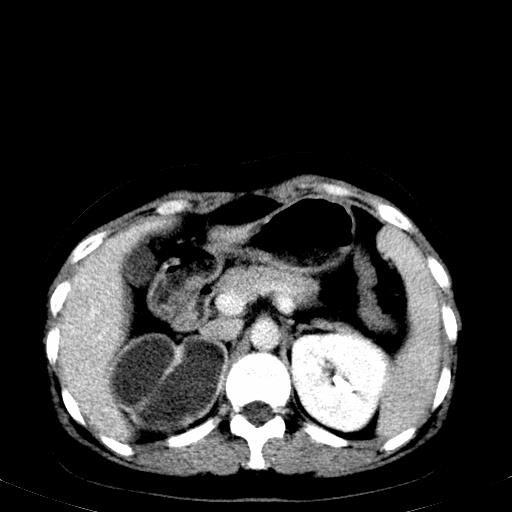

患者体检发现右肾体积增大,怀疑右肾积水

右肾多发囊肿,左肾、左输尿管结石

右肾重度积水,以肾盏积水明显,有分隔,上段输尿管轻度扩张,管壁增厚,考虑肾结核可能,请结合尿检查,胸部拍片排除肺结核。

右侧肾积水、左侧肾结石

右侧肾积水、左侧肾结石  ,要排除右肾结核可能。

右肾重度积水,建议ct向下扫描或逆行造影,左肾及左输尿管结石 .

右侧肾积水、左侧肾结石 ,原因待查

患者尿常规正常,b超未发现明显结石,自身也无明显感觉异常。

请问多囊肾与肾积水怎么鉴别